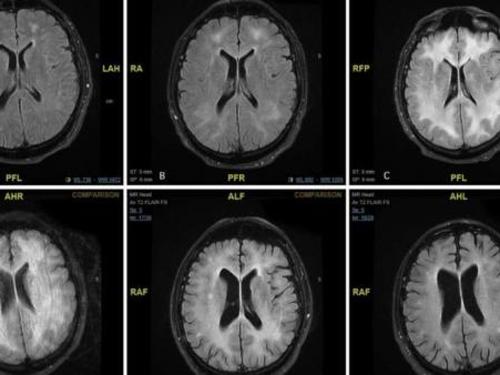

Revelan Imágenes De Cómo La Cocaína Come El Cerebro De Un Adicto La cocaína es una droga que ha causado preocupación a nivel mundial debido a su impacto en la salud de quienes la consumen. ¿sabías que tiene efectos devastadores en el cerebro? en este artículo, te explicaremos cómo la cocaína afecta al cerebro y cuáles son sus consecuencias a corto y largo plazo. El consumo de drogas trae consecuencias extremadamente negativas para todo el organismo, pero especialmente para el más importante, que es el cerebro. este y el corazón son los primeros órganos.

Impactante Así Devora El Cerebro La Cocaína Consumida Una Resonancia

Cocaína Así Devora El Cerebro Su Consumo